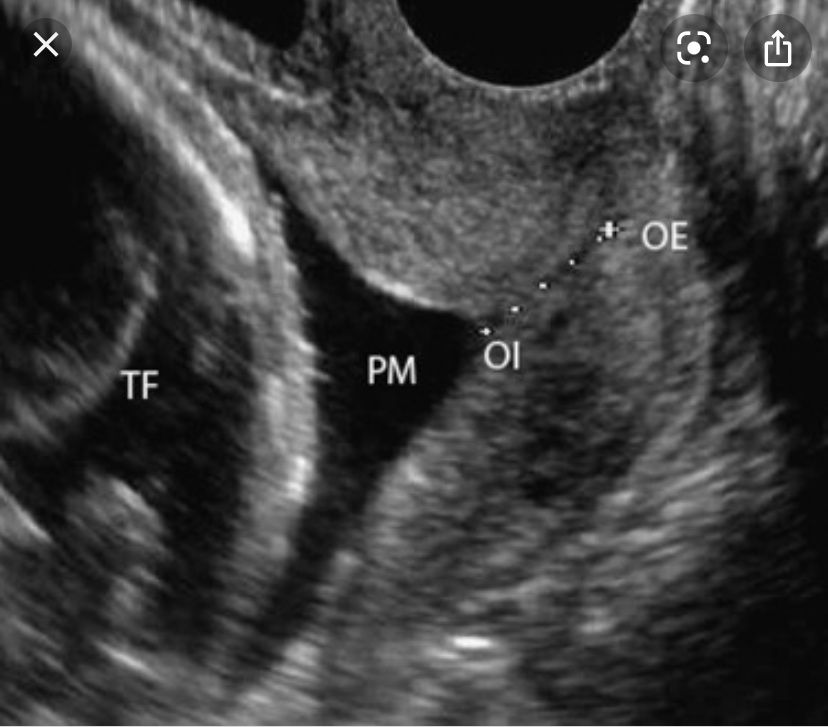

Там по разному может быть. Ну вот из Гугла, например, V-образное открытие внутреннего зева. TF - голова плода, OI - внутренний зев, OE - внешний зев, OI-OE, соответственно, длина цервикального канала, точнее того, что от него осталось из-за открытия.